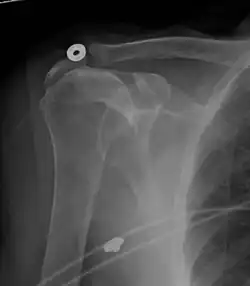

Рентгеновский снимок

Рентгеновская проекционная рентгенография не может напрямую выявить разрывы вращающей манжеты, «мягких тканей», и, следовательно, обычные рентгеновские лучи не могут исключить повреждение манжеты. Однако косвенные доказательства патологии можно увидеть в случаях, когда одно или несколько сухожилий подверглись дегенеративной кальцификации (кальцифицирующий тендинит). Головка плечевой кости может мигрировать вверх (высоко расположенная головка плечевой кости) вследствие разрыва подостной или комбинированной надостной и подостной мышцами.[44] Миграцию можно измерить расстоянием между:

- Линией, пересекающая центр линии между верхним и нижним краями суставной поверхности суставной впадины (синяя на изображении).

- Центром наиболее подходящего круга, расположенный над суставной поверхностью плечевой кости (зеленый на изображении)

Обычно первый расположен ниже второго, и поэтому переворот указывает на разрыв вращательной манжеты.[44] Длительный контакт между высоко расположенной головкой плечевой кости и акромионом над ней может привести к обнаружению на рентгеновских снимках износа головки плечевой кости и акромиона или вторичного дегенеративного артрита плечевого сустава, называемого артропатия манжеты.[43] Случайные рентгенологические находки костных шпор в соседнем акромиально-ключичном суставе могут показать костную шпору, растущую от внешнего края ключицы вниз к вращающей манжете. На нижней стороне акромиона также можно увидеть шпоры, которые, как когда-то считали, вызывают прямое истирание вращающей манжеты из-за контактного трения, концепция, которая в настоящее время считается спорной.